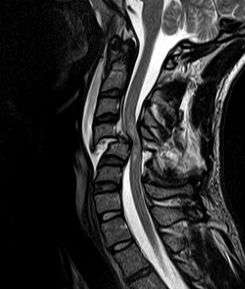

| MRI of fractured and dislocated neck vertebra that is compressing the spinal cord | |